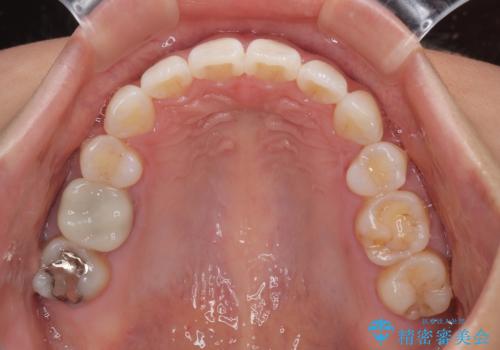

舌の突出癖改善のためのトレーニングをしっかりと実践してくださり、2年強の治療期間でしっかりと仕上げることができました。

- 前歯が突出して、眠るときに口が開いてしまうことを気にして来院された患者様です。

横から見た際の口元の飛び出した印象も改善したいとのことで、上下左右の第一小臼歯4本を抜歯し、ワイヤー装置にて抜歯矯正を行うこととしました。